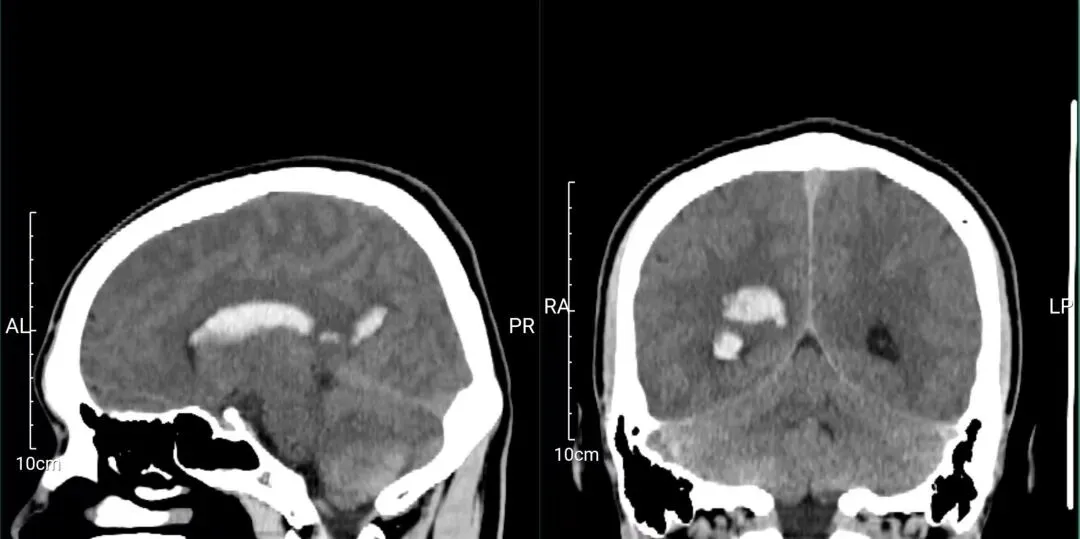

检查结果很快出来——脑出血。

患者小余头颅CT检查结果明确提示:脑出血。 受访者供图。